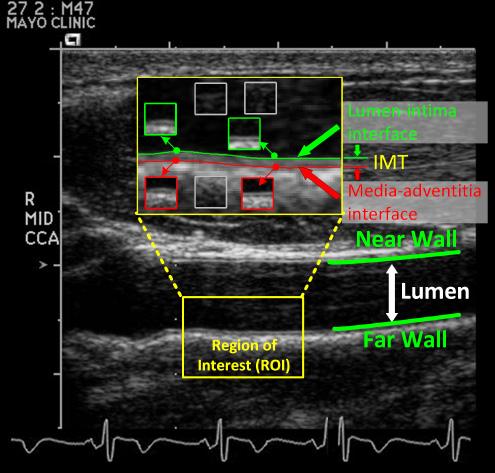

A three-way Convolutional Neural Network operating on medical imaging

The researchers conducted experiments in four sectors of medical imaging related to colonoscopy, and found that their fine-tuned, pre-trained CNNs either outperformed or equalled the performance of scratch-trained CNN datasets. The field of research chosen - medical imaging - represents a formidable initial challenge for such a 'pre-baked' system. If replicable across other (less-critical) fields, the idea promises a significant boon to the evolution of Convolutional Neural Networks in the post-GPU age.